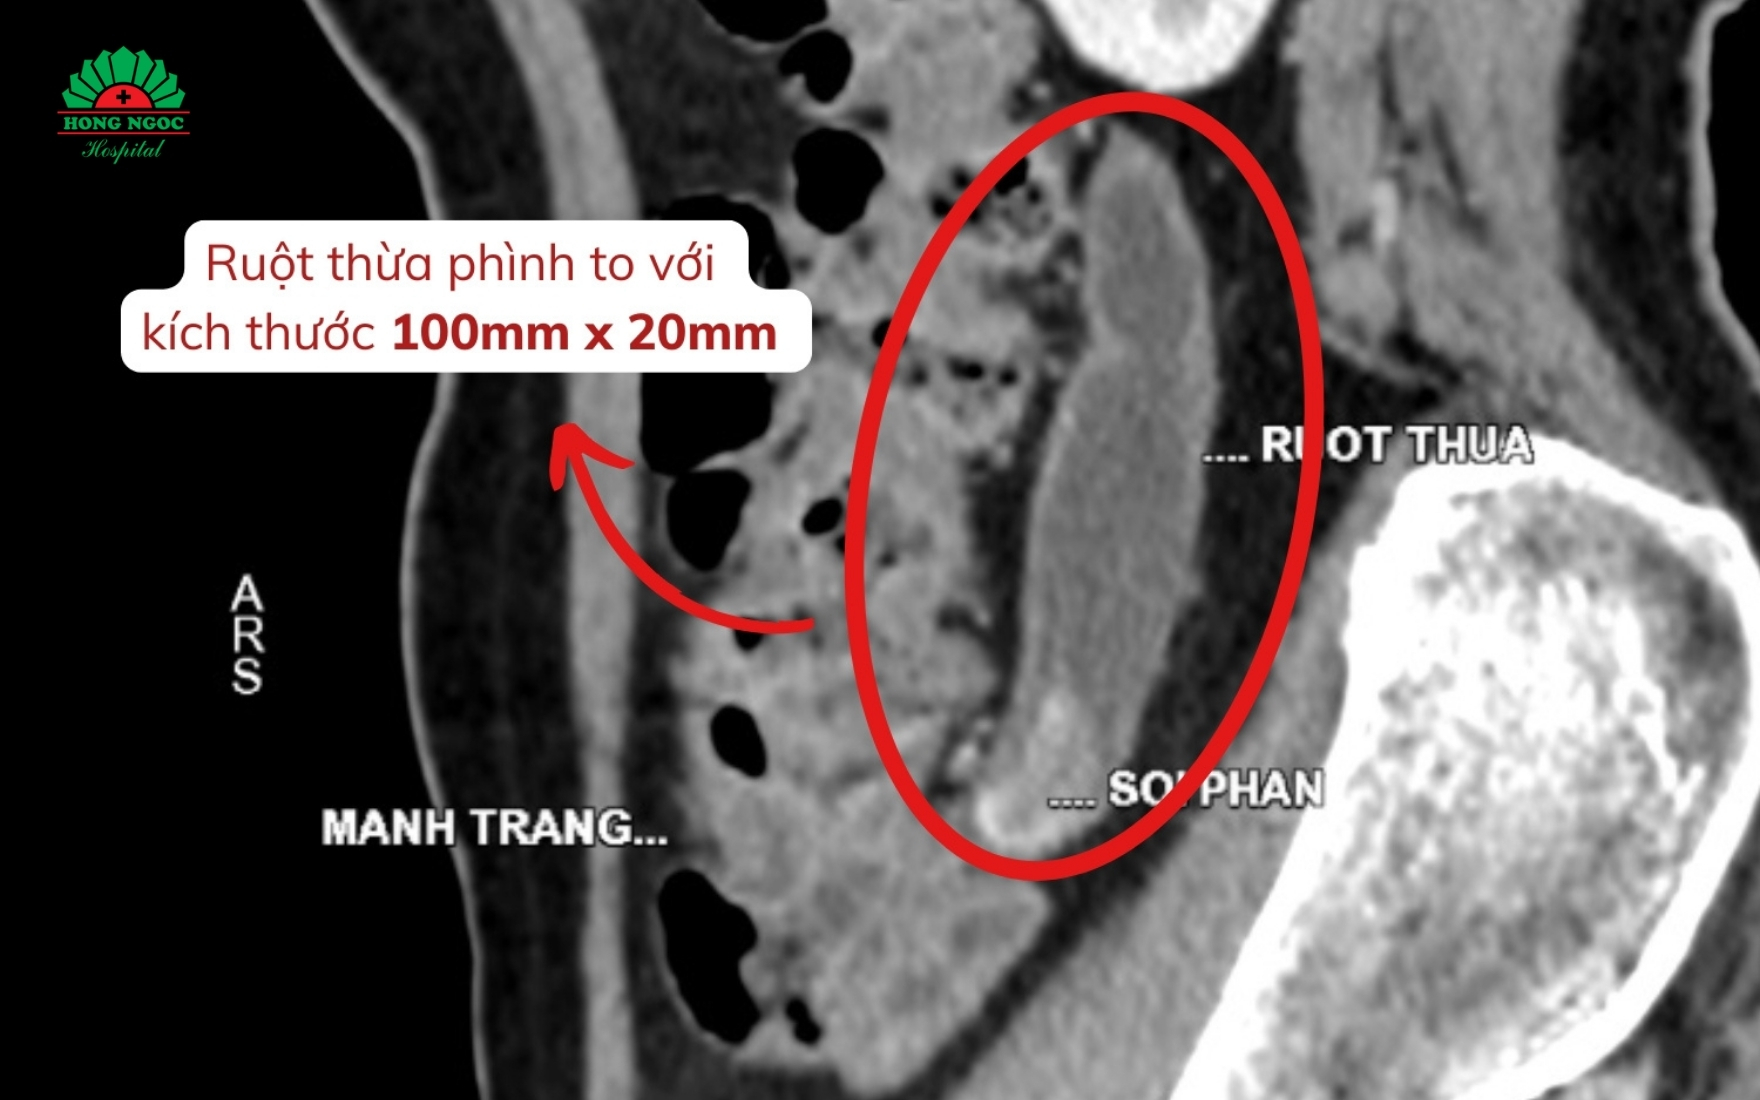

Tại BVĐK Hồng Ngọc, bệnh nhân được chỉ định siêu âm, chụp CT ổ bụng và thực hiện các xét nghiệm cận lâm sàng cần thiết. Kết quả cho thấy kích thước ruột thừa to bất thường với đường kính 22mm, gấp 4 lần bình thường, bên trong ruột thừa có tổ chức u nhầy. Bác sĩ chẩn đoán bệnh nhân mắc u nhầy ruột thừa và chỉ định phẫu thuật.

Kết quả chụp CT ổ bụng phát hiện ruột thừa phình to, bên trong có tổ chức u nhầy

- Chụp cắt lớp vi tính (CT-scan): Được coi là công cụ chẩn đoán tin cậy nhất, CT-scan giúp nhận diện các đặc điểm điển hình của u nhầy, đồng thời xác định rõ vị trí cũng như kích thước khối u.